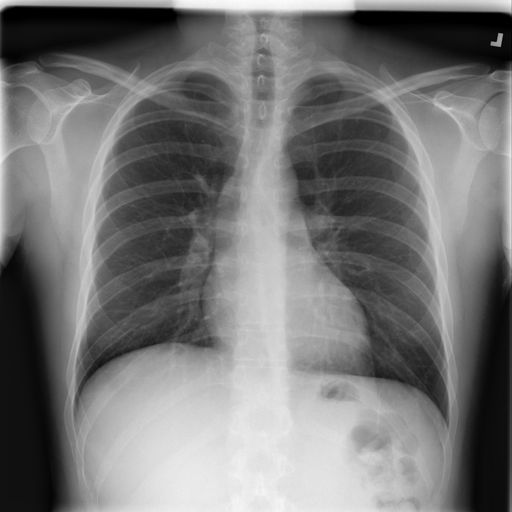

Complex case X-ray

Complex High Uncertainty

High Uncertainty Case

Male, 58y • Dyspnea, chest pain, diabetes

TB prob 84.8% but high uncertainty (std=0.16). Tests model's uncertainty quantification and edge-case handling.

ComorbidityEdge Case